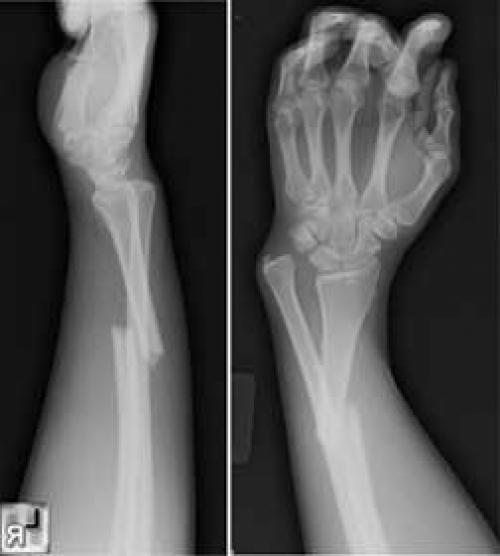

Рис.3 а. схематическое изображение перелома Коллеса и Смита; б. на рентгенограммах перелом диафиза лучевой и локтевой кости в с/3 со смещением.